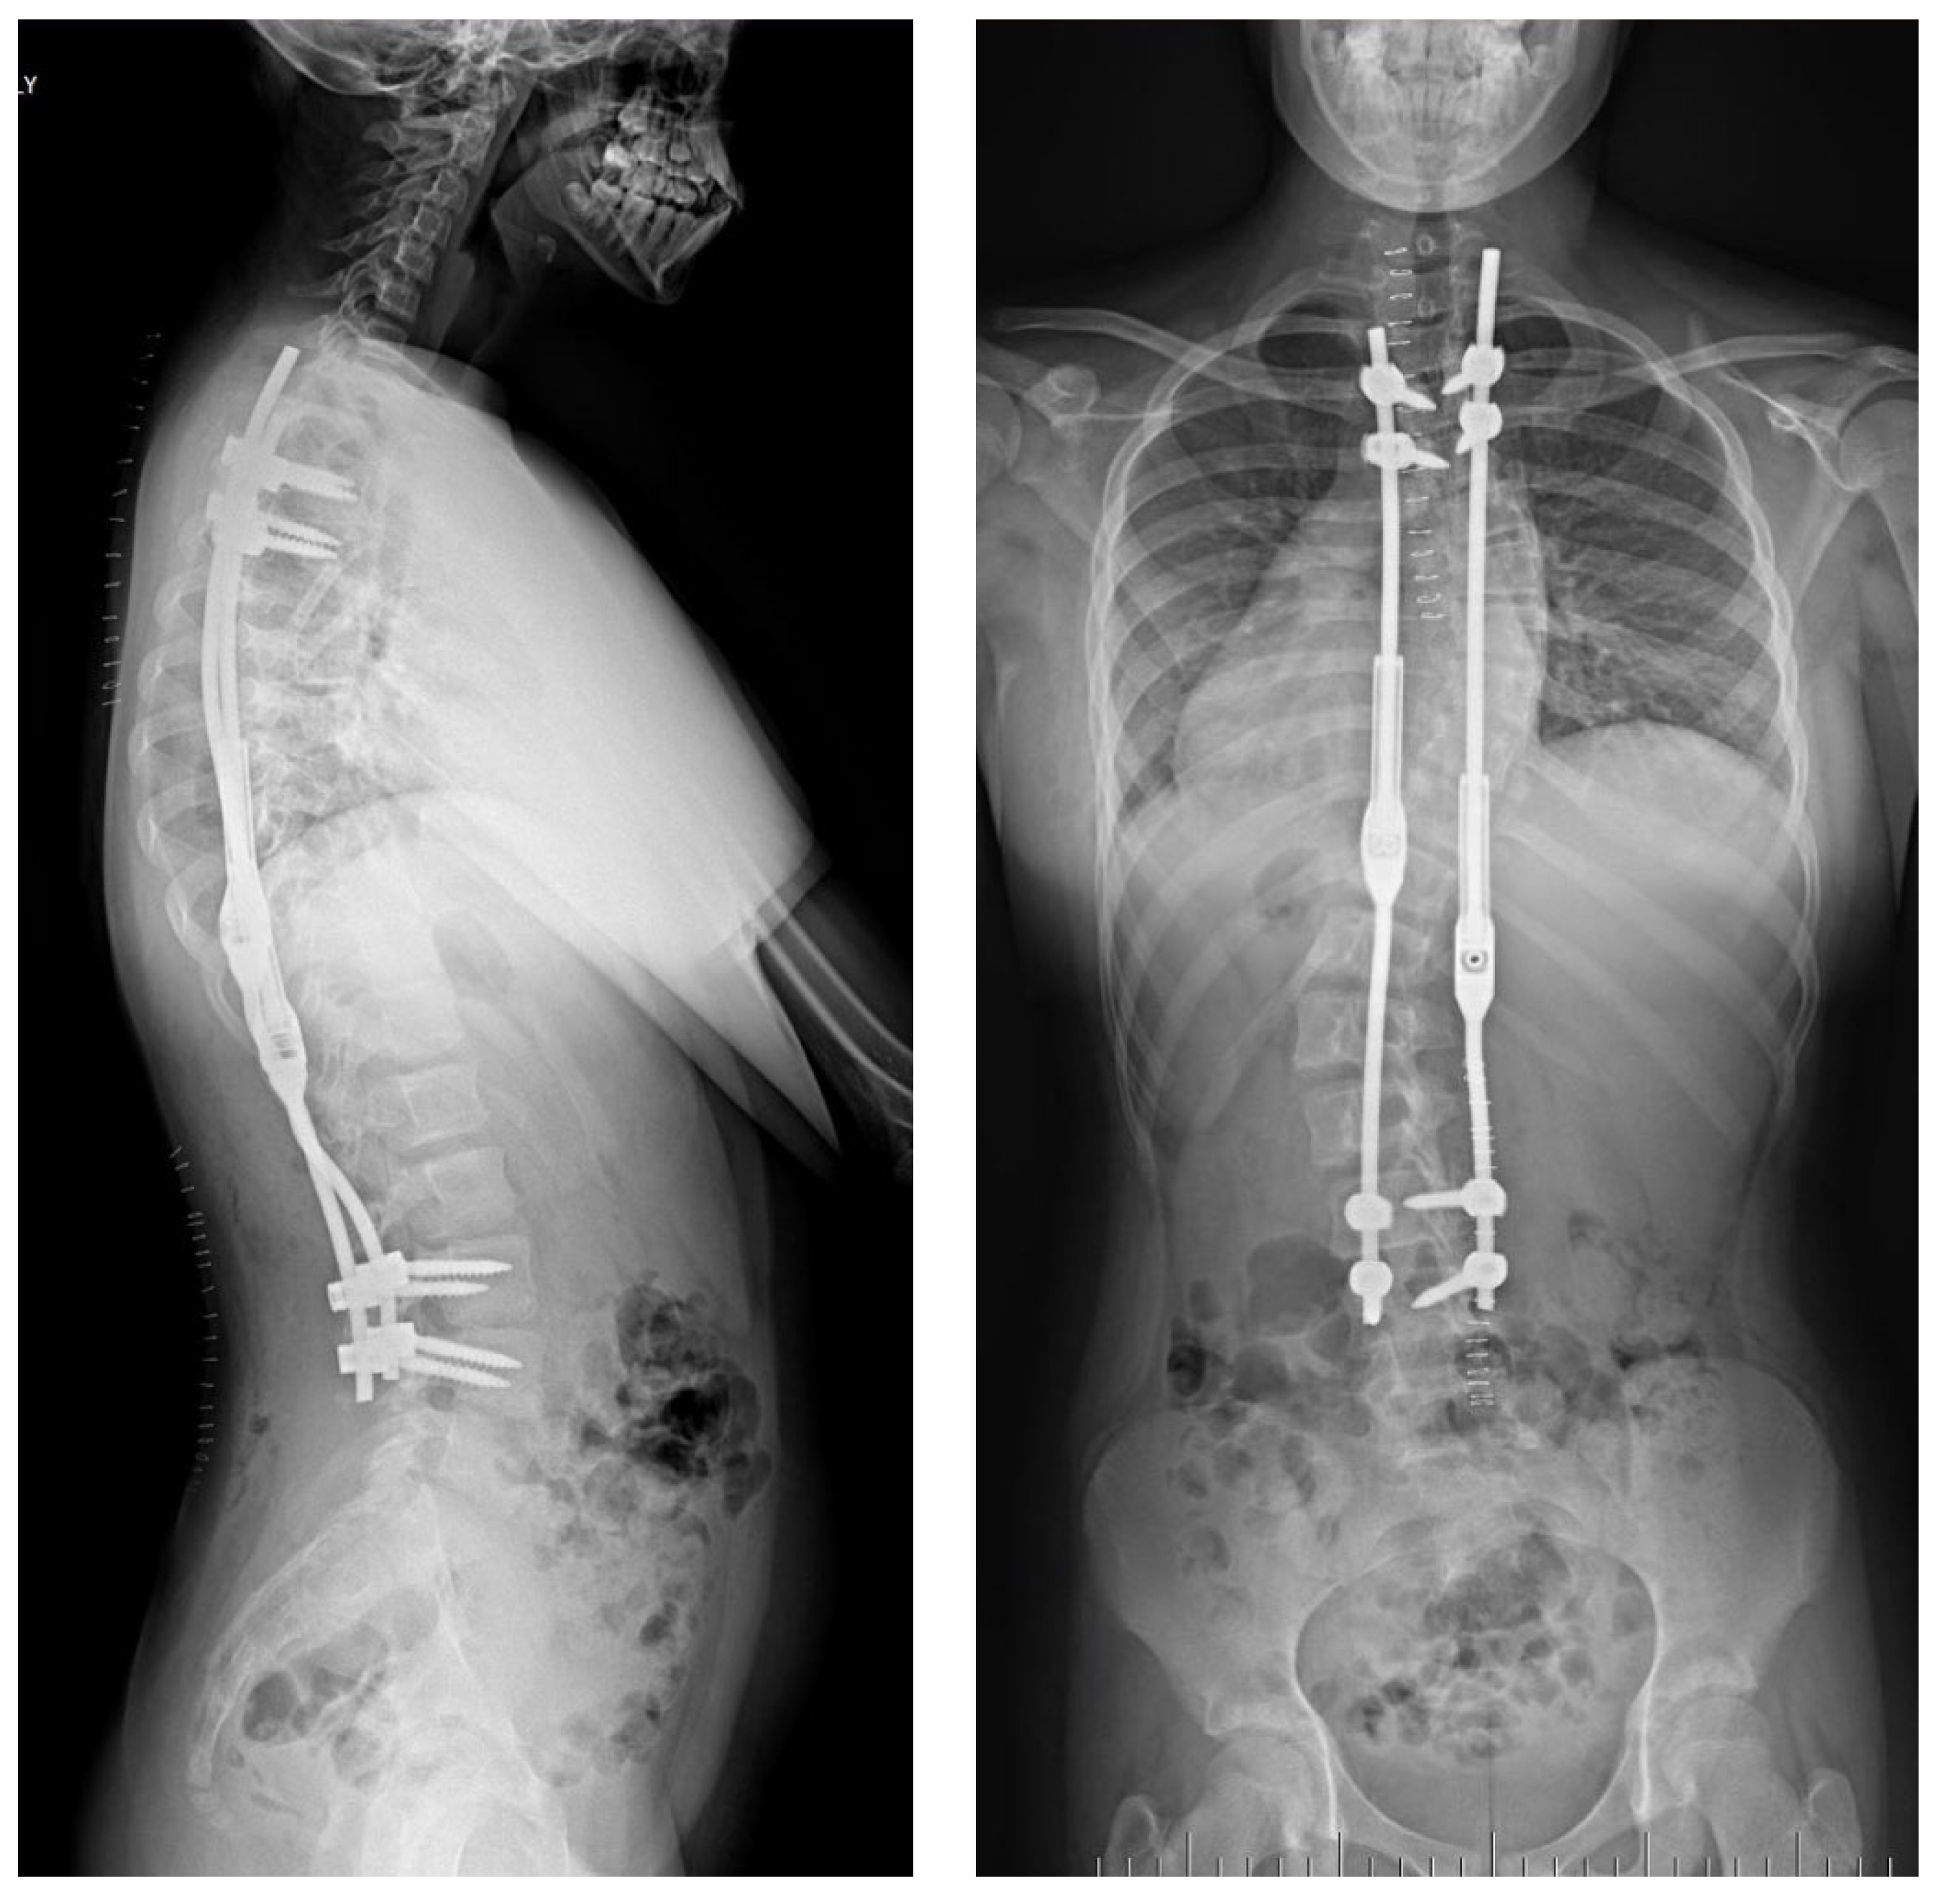

2.3. Example of Congenital Kyphosis